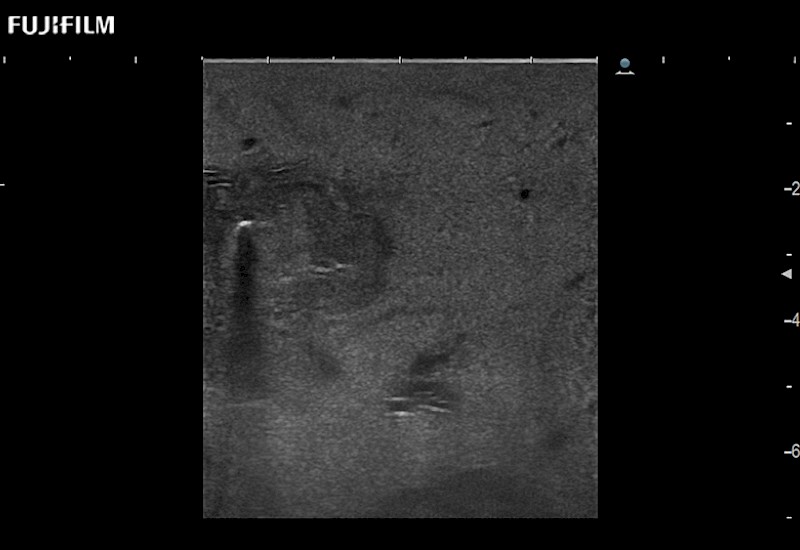

Extraordinary high-resolution digital imaging

for use during open and laparoscopic procedures: Tumor localization & staging, Ablation, Resection, Biopsy, Transplant, Abdominal exploration, Robotic surgery

- Instant feedback on tumor margin delineation

- Valuable information to guide tumor resections

- Instant feedback on tumor margin delineation

- Exceptional near and far-field resolution

- Instant feedback on tumor margin delineation

- Instant feedback on tumor margin delineation

- Instant feedback on tumor margin delineation

- Instant feedback on tumor margin delineation

- Valuable information to guide tumor resections

- Instant feedback on tumor margin delineation

- Valuable information to guide tumor resections

- Instant feedback on tumor margin delineation

- Valuable information to guide tumor resections

- Instant feedback on tumor margin delineation

- Valuable information to guide tumor resections

- Instant feedback on tumor margin delineation